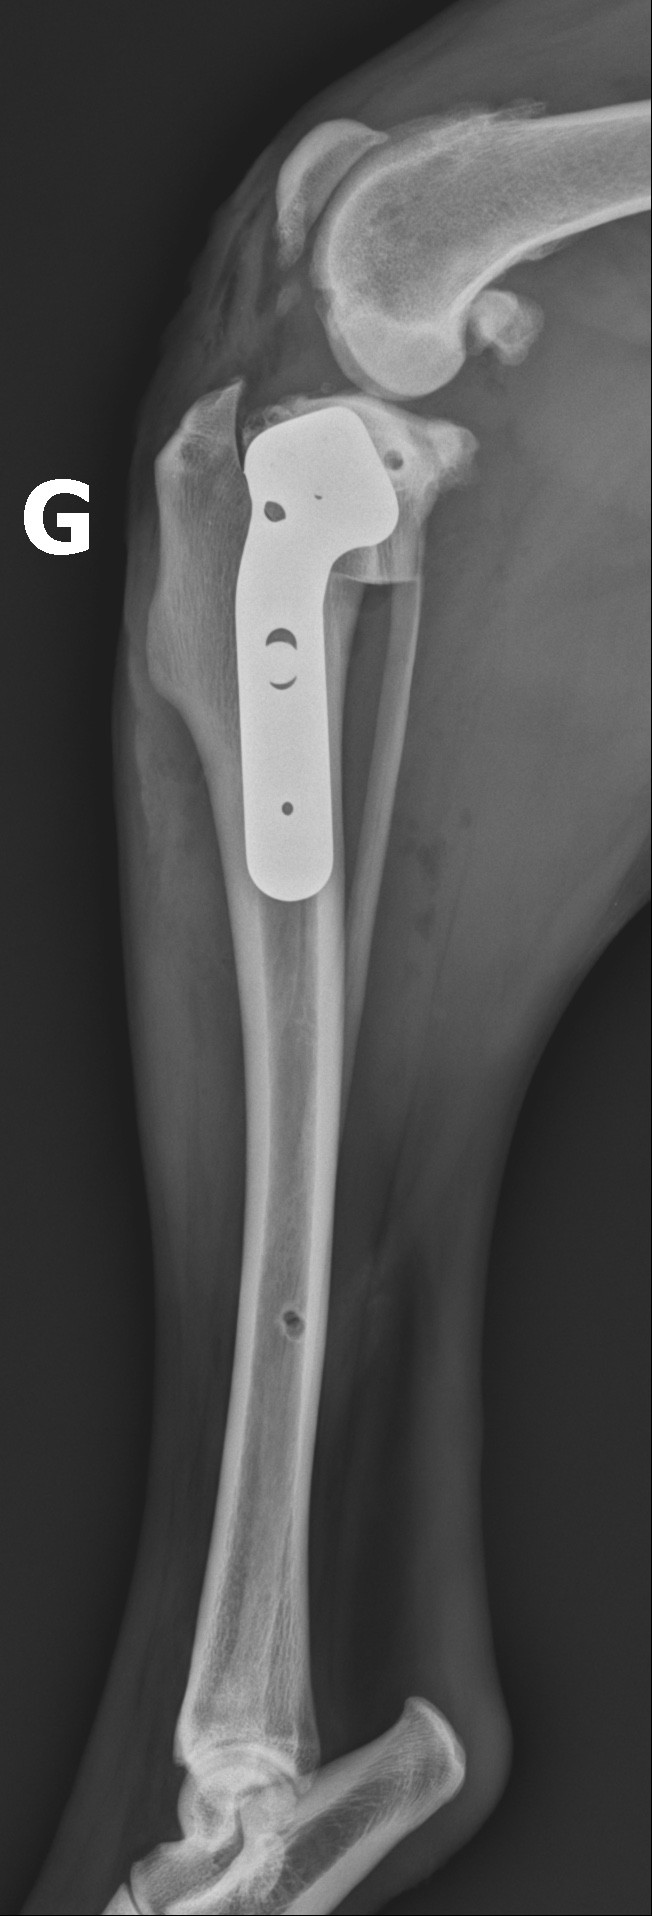

Sous anesthésie générale, le vétérinaire réalise une coupe circulaire dans le tibia, fait pivoter l’os pour obtenir l’angle souhaité, puis fixe la position à l’aide d’une plaque et de vis en titane ou acier chirurgical.

Vue radiographique de profil du grasset gauche suite à la réalisation d'une TPLO dans le traitement d'une rupture du ligament croisé crânial